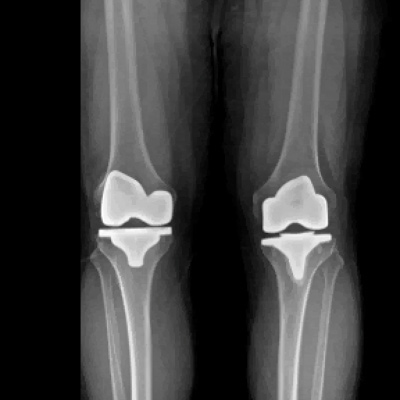

Axial View Total Knee Replacement

R knee: Mechanical Alignment

L knee: Kinematic Alignment

Kinematic Alignment Total Knee Replacement